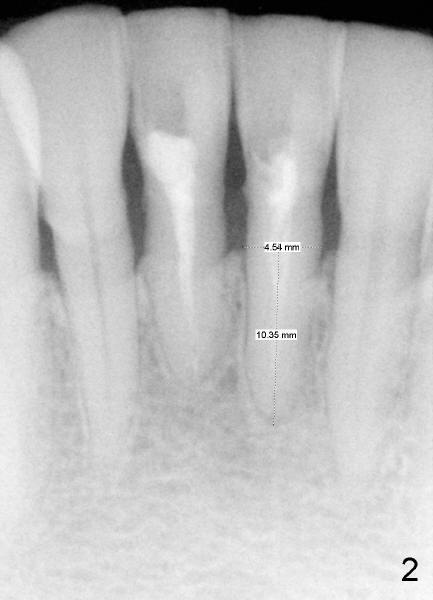

Two PAs were taken at different angulations (Fig.1,2 vs. 3,4).  The shortest M-D width of the tooth #24 is 3.16 mm (Fig.4 vs. 4.54 mm in Fig.2, probably close to the B-L width).

There is plenty of dimension in height.  What is the appropriate size of the implant?  How to handle the discrepancy of M-D and B-L widths?